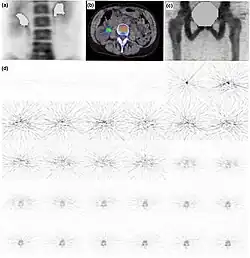

Deconvolution method

The method was first described by Williams et al. in the clinical context.[50] The method was used by numerous other studies.[51][52][53] This is perhaps the simplest of all the mathematical methods for the calculation of Ki but the one most sensitive to noise present in the data. A tissue TAC is modelled as a convolution of measured arterial input function with IRF, the estimates for IRF are obtained iteratively to minimise the differences between the left- and right-hand side of the following Equation:

where, is a convolution operator, Cbone(t) is the bone tissue activity concentration of tracer (in units: MBq/ml) over a period of time t, Cplasma(t) is the plasma concentration of tracer (in units: MBq/ml) over a period of time t, and IRF(t) is the impulse response of the system (i.e., a tissue in this case). The Ki is obtained from the IRF in a similar fashion to that obtained for the spectral analysis, as shown in the figure.